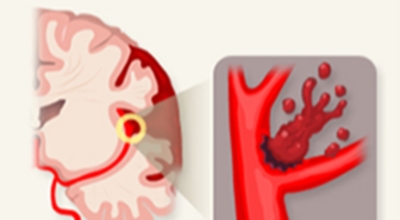

만약 이런 혈관이 파열되고, 공급되던 산소가 누출되어 뇌 조직에 도달하지 못하면 어떻게 될까요? 혈액이 고이며 뇌에 부담(압력)을 주며, 응급조치가 없이 3~4분 이상 산소가 결핍된 상태가 지속되면 뇌세포는 죽습니다. 그러면 함께 영향을 받는 신경 세포가 제어능력을 잃게 되고, 우리 몸의 기능도 함께 손상되는 것으로 보입니다.

뇌출혈 전조증상을 놓쳐 뇌출혈이 발생하게 되면 발작 직후 안정을 취해야 합니다. 뇌부종을 가라앉히기 위해 약물 요법으로 고농도 포도당, 덱사메타존, 만니톨 등을 투약할 수 있고 뇌의 혈액 순환을 회복시키는 주사와 지혈제, 진정제 등을 사용할 수 있습니다. 혈종의 크기가 중등도 이상으로 마비 증세가 있으면 머리뼈에 작은 구멍을 내서 관을 넣어 혈종을 뽑아내는 수술을 시행할 수 있습니다.

혈압성 뇌출혈인 경우 혈종의 크기가 작으며 환자의 증상이 경미하면 약물 치료를 시행합니다. 혈종의 크기가 매우 크며 뇌가 심하게 부어오를 때는 응급으로 머리뼈를 절개해 혈종을 빠르게 제거해야합니다. 응급조치가 늦어지면 뇌압이 상승해 의식을 잃고 사망에 이를 수 있기 때문인데요 이렇게 증상이 심할 때는 수술이 잘 되었더라도 예후가 좋지 못할 때가 많다고 합니다.